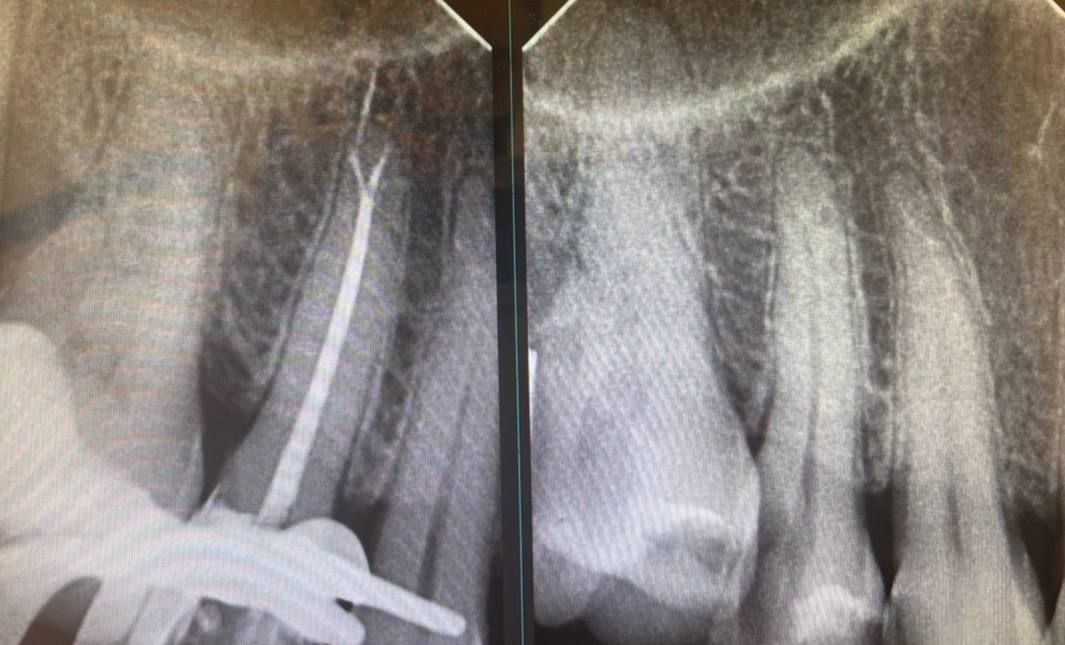

Jestem lekarzem dentystą zajmującym się stomatologią zachowawczą oraz leczeniem kanałowym pod mikroskopem (endodoncja mikroskopowa). W swojej pracy stawiam na kompleksowe podejście do zdrowia jamy ustnej – dokładną diagnostykę, skuteczne leczenie oraz profilaktykę.

Specjalizuję się w leczeniu próchnicy, odbudowie zębów oraz leczeniu kanałowym, w tym leczeniu kanałowym pod mikroskopem, które pozwala na bardzo precyzyjne oczyszczenie i opracowanie kanałów korzeniowych. Dzięki zastosowaniu mikroskopu możliwe jest skuteczne leczenie nawet bardziej skomplikowanych przypadków oraz powtórne leczenie kanałowe (reendo).

Jestem bardzo zadowolona z leczenia u Pani doktor. Mój przypadek był naprawdę trudny, bo kanały były już bardzo zniszczone i nawet sugerowano usunięcie zęba. Pani doktor uratowała mój ząb, co wymagało ogromnej precyzji i doświadczenia. Leczenie zostało mi krok po kroku wytłumaczone, dzięki czemu czułam się spokojna i świadoma tego, co się dzieje.

Sam zabieg przebiegł w komfortowej i bezstresowej atmosferze, bo było dla mnie bardzo ważne. Ząb czuje się świetnie!

Jestem bardzo wdzięczna i z całego serca polecam!• ARTMED GROUP -Centrum Stomatologii i Implantologii • Leczenie endodontyczne •